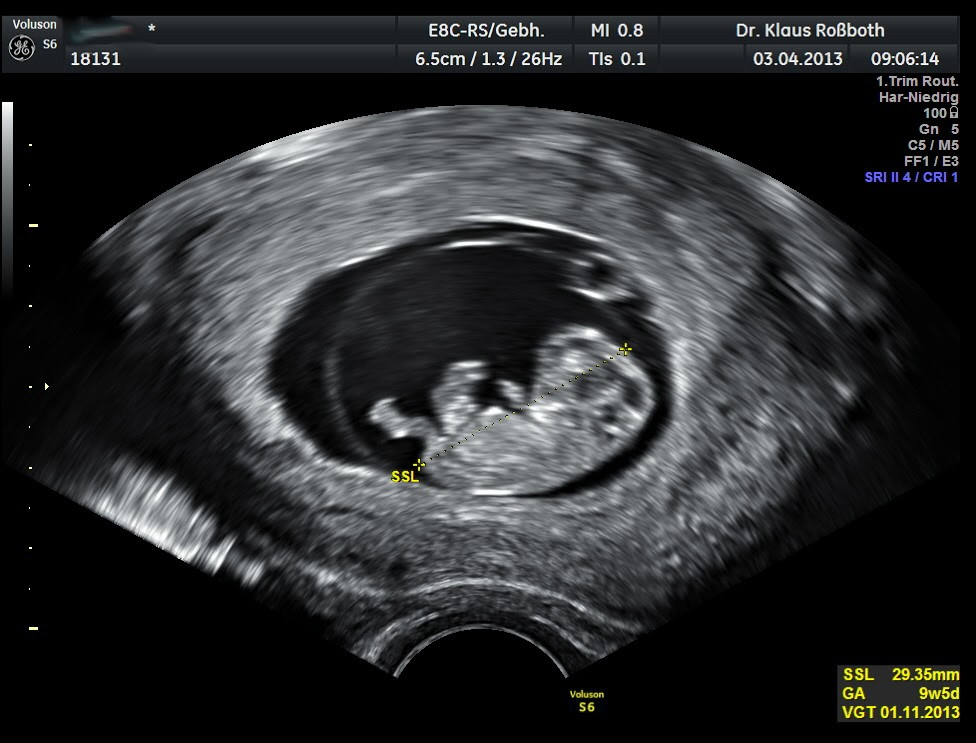

SSW es ist jetzt 47mm groß der errechnete Termin ist de 11413. Es misst bereits 6-7 mm Scheitel-Steiß-Länge. Schwangerschaftsmonat geht zu Ende.

SSW beginnt die Entwicklung des Gesichts Bild bei 74 Größe und Entwicklung des Embryos. Ultraschall in der 4. SSW ist der Embryo 16 Millimeter groß.

An den Stellen wo später die Augen sein werden kann man schwarze Punkte erkennen. SSW 74 Dottersack Fruchthöhle vorhanden Embryo nicht verhanden.

In der sogenannten Fruchthöhle sind der Dottersack und dein Embryo Zygote sehr gut zu erkennen. In dieser Woche kann man eine Schwangerschaft im Ultraschall noch nicht sehen da seit der. Es misst bereits 6-7 mm Scheitel-Steiß-Länge. SSW 74 Dottersack Fruchthöhle vorhanden Embryo nicht verhanden. Oh schön Ich kann das gut verstehen. Schwangerschaftswoche bereits die Gesichtszüge deines Babys erkennen. An den Stellen wo später die Augen sein werden kann man schwarze Punkte erkennen.